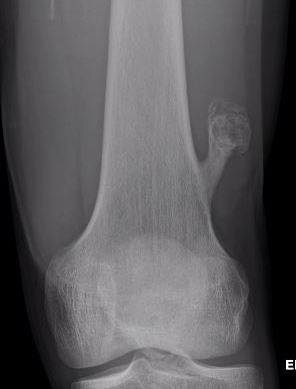

Proximal humerus

Bae et al J Pediatr Orthop 2014

- 31 patients with proximal humerus osteochondromas

- anterior / lateral / posterolateral debulked 92%

- posteromedial debulked 68%

- recurrence 2/31 (6.5%)